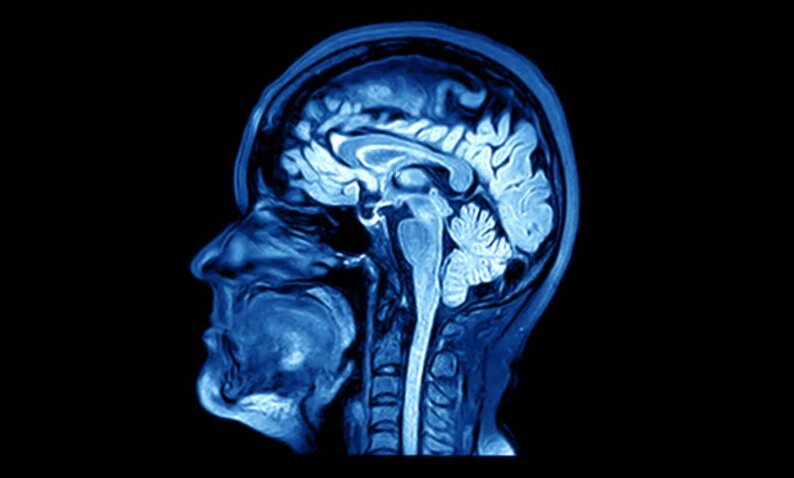

Часто в быту мы что-то да забываем или попросту не можем запомнить. Думаю, эта проблема встречалась у каждого. И любой задумывался над тем, как бы улучшить свою память и запоминать гораздо больше информации. Ученых эта проблема волнует не в последнюю очередь, потому что существует куча болезней, связанных с потерей долговременной памяти. Научные работники стараются придумать новый метод или прибор для улучшения памяти В Соединенных Штатах Америки протестировали имплант-электростимулятор для мозга, который в теории улучшает человеческую память на 15%. Американские ученые провели первый этап тестирования своего устройства, которое улучшало память человека при помощи электостимуляции мозга. По словам ученых, память подопытных улучшалась и они запоминали значительно больший объем информации. Этот способ стимуляции мозга планируют использовать для людей с черепно-мозговыми травмами, влияющими на память. Метод работы этого стимулятора использовался ранее для лечение болезни Паркинсон